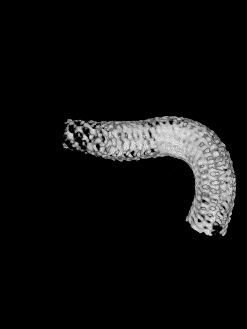

Marksman™ 导管0.014" 200cm 微导丝Pipeline™ Flex血流导向密网支架 PED-325-25

Pipeline™ Flex 血流导向密网支架

Pipeline™ Flex 血流导向密网支架于密网支架充分打开,所以从外缘向内缘回拉,让密网支架位于血管中轴。

Pipeline™ Flex 血流导向密网支架密网支架充分打开。